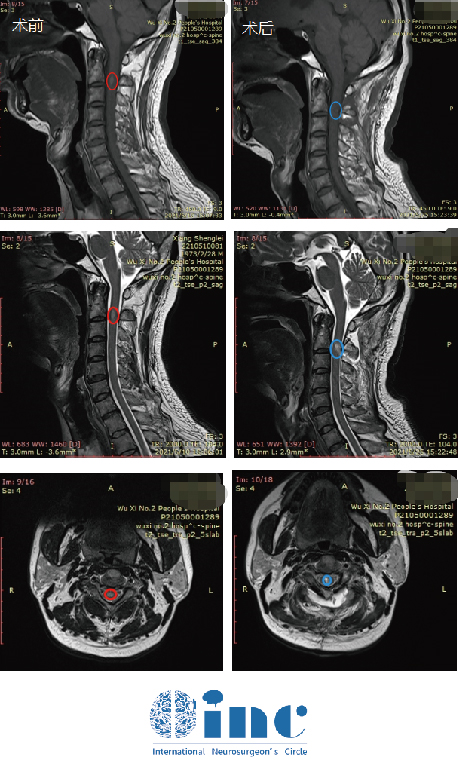

(患者术前病变)

全切肿瘤后的颈髓